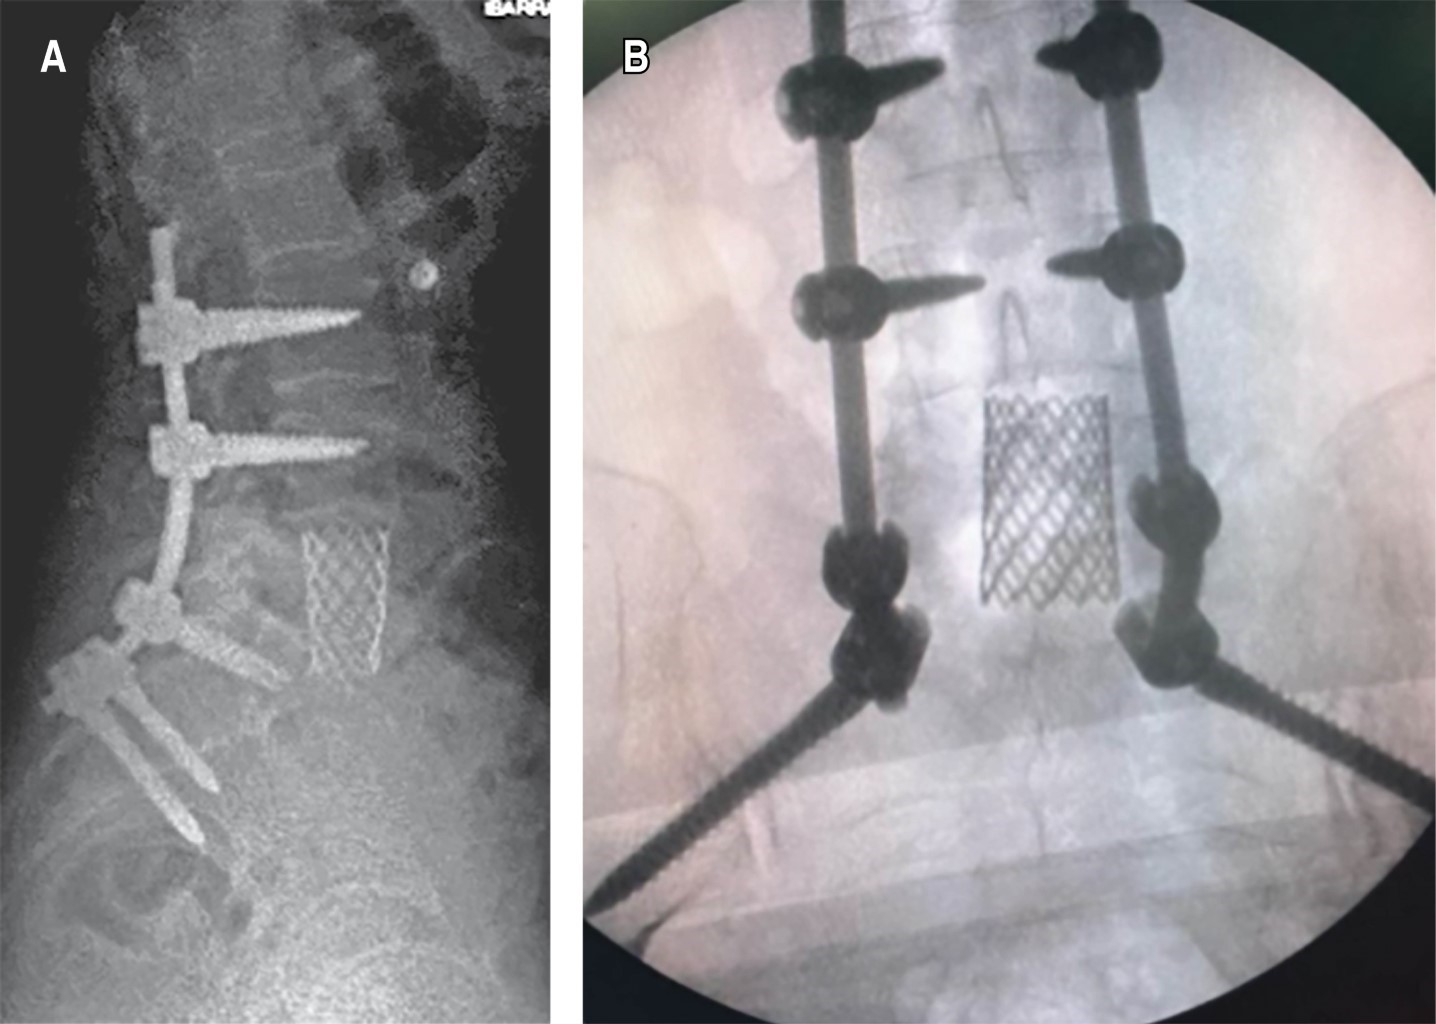

Recibimos paciente en consultorio con facies claras de dolor, sin tolerar la deambulación ni la sedestación, fuerza muscular para ambos miembros pélvicos 3/5 en todos los grupos musculares interferida por la generación de dolor a la movilización. Refiere adecuado control de esfínteres. Se solicitan radiografías en doble proyección como método de diagnóstico inicial, en donde se observa lesión en cuerpo vertebral L5, con aparente destrucción del mismo, por lo que se decide complementar el protocolo de estudio mediante serie ósea metastásica, tomografía axial computarizada (TAC) abdominopélvica y de columna-tórax y resonancia magnética simple de columna. A la revisión de la TAC de columna se observa la presencia de lesión lítica de quinto cuerpo vertebral lumbar, con afectación del muro posterior (Figura 1). En la resonancia magnética se describe la existencia de lesiones hiperintensas en L5 ocasionando compresión e invasión hacia canal medular de aproximadamente 70%. Considerando el aumento de la sintomatología más el grado de compresión, se considera realizar tratamiento quirúrgico consistente en descompresión mediante lumbotomía de L5 por abordaje anterior más colocación de malla con injerto autólogo e instrumentación transpedicular L3-S1 con aumento a iliacos y envío de la muestra obtenida por corpectomía a patología y cultivo (Figura 2). Se obtienen resultados de patología a las dos semanas posteriores, en donde se reporta muestra macroscópica compatible con carcinoma folicular de tiroides, motivo por el cual se solicita valoración por servicio de oncología y oncocirugía, en donde se realiza como complemento de estudio ultrasonido Doppler de tiroides objetivándose presencia de nódulos tiroideos, por lo que se inicia protocolo quirúrgico para realización de tiroidectomía total. Después de ambos procedimientos quirúrgicos, la paciente muestra adecuada evolución clínica sin datos de proceso infeccioso agregado iniciando deambulación progresiva y con seguimiento por medio de la consulta externa por servicios correspondientes (Figura 3).